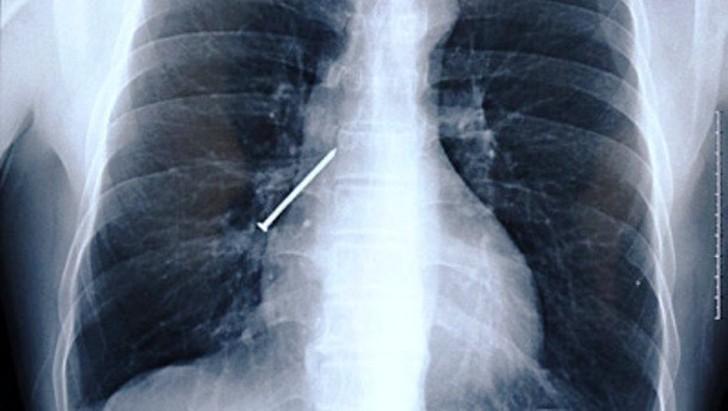

10. Гвоздь.